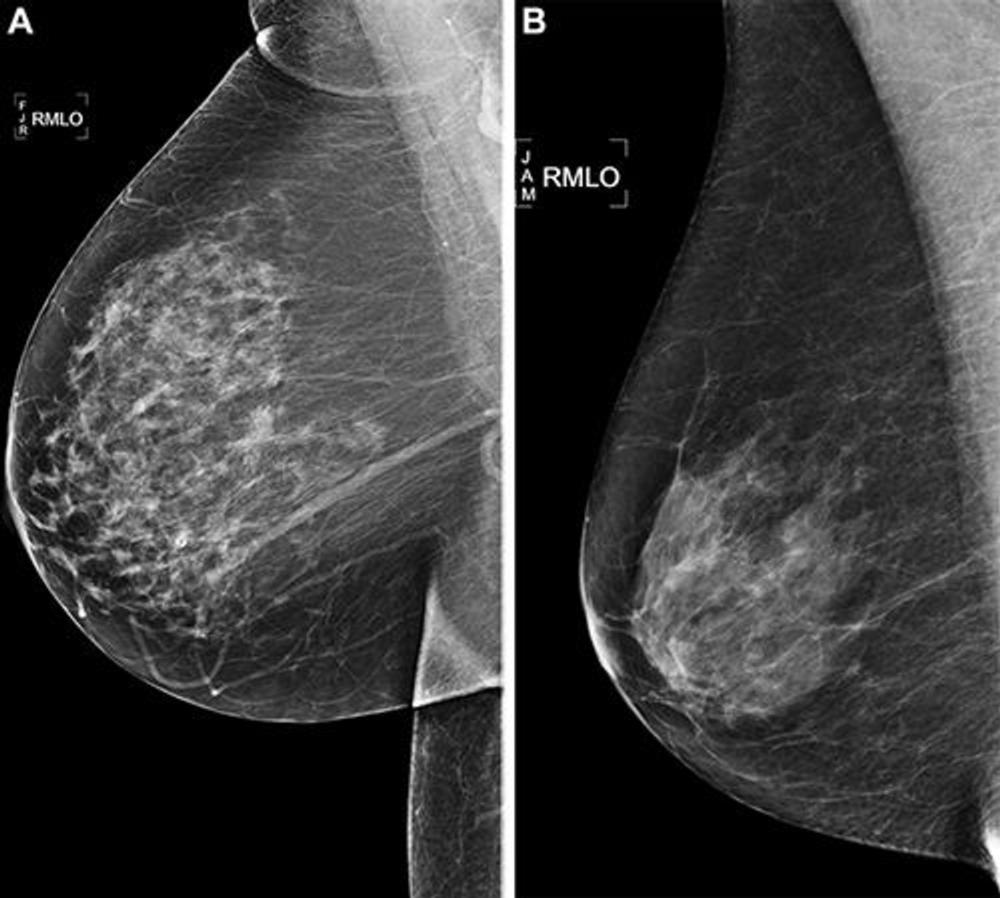

Figure 3. Right medial lateral oblique (RMLO) screening mammograms show negative results from 2016 in (A) a 73-year-old woman with Mirai artificial intelligence (AI) risk score with more than 90th percentile risk who developed right breast cancer in 2021 at 5 years of follow-up and (B) a 73-year-old woman with Mirai AI risk score with less than 10th percentile risk who did not develop cancer at 5 years after 5 years of follow-up.